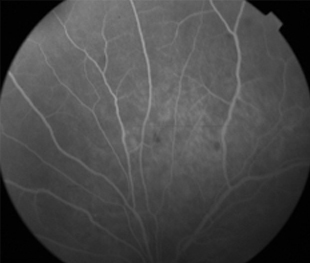

Angiografía OI

- Angiografía: teñido arterial, escape capilar, más tardíamente, no perfusion arteriolar y venular con teñido de las paredes vasculares y dilatación venosa.